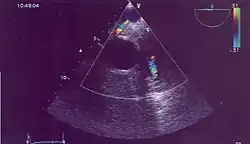

Possible communication between left coronary artery and pulmonary artery in a 45-year-old woman with Bland-White-Garland syndrome.

Historically ALCAPA was diagnosed with conventional angiography. Today echocardiography is easily used. It can provide direct visualisation of the anomalous coronary artery and other associated structural abnormalities, and it can also assess myocardial function. The use of pulse and color-flow doppler can sometimes visualise reversal flow in the pulmonic artery. Other non-invasive methods used are computed tomography (CT) as well as magnetic resonance imaging (MRI), which enable a direct visualisation of the arteries as well as the myocardial viability.[3]